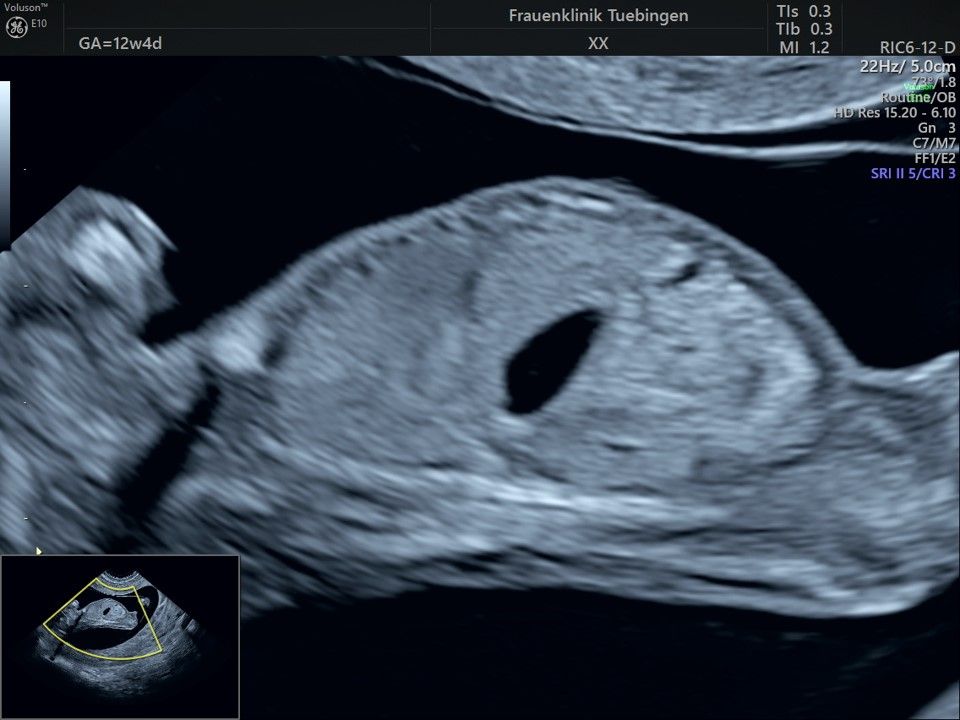

Bauchwanddefekt

Obwohl der Fet zu diesem Zeitpunkt erst zwischen 5 und 8cm groß ist, lassen sich bereits etwa die Hälfte aller schwerwiegenden Fehlbildungen erkennen bzw. ausschließen. Sollten wir eine Auffälligkeit sehen, werden wir mit Ihnen den Befund und das weitere Vorgehen ausführlich besprechen.

Es sollte berücksichtigt werden, dass strukturelle/anatomische Fehlbildungen (z.B. angeborene Herzfehler) deutlich häufiger auftreten. Bei etwa 2-3% (1:30 - 1:50) der Feten werden Fehlbildungen gefunden. Diese können isoliert, d.h. ohne Chromosomenstörung auftreten. Sie werden aber gehäuft bei Trisomien und andersartigen Veränderung des Erbguts gefunden. Daher ist eine detaillierte Ultraschalluntersuchung im Rahmen der Risikobeurteilung unerlässlich. Sollte eine Fehlbildung erkannt werden, so ist eine Risikoberechnung für Trisomie 21 alleine nicht ausreichend. Hier sollte eher an eine Fruchtwasser- oder Mutterkuchenpunktion gedacht werden, um eine Chromosomenstörung erkennen oder ausschließen zu können.